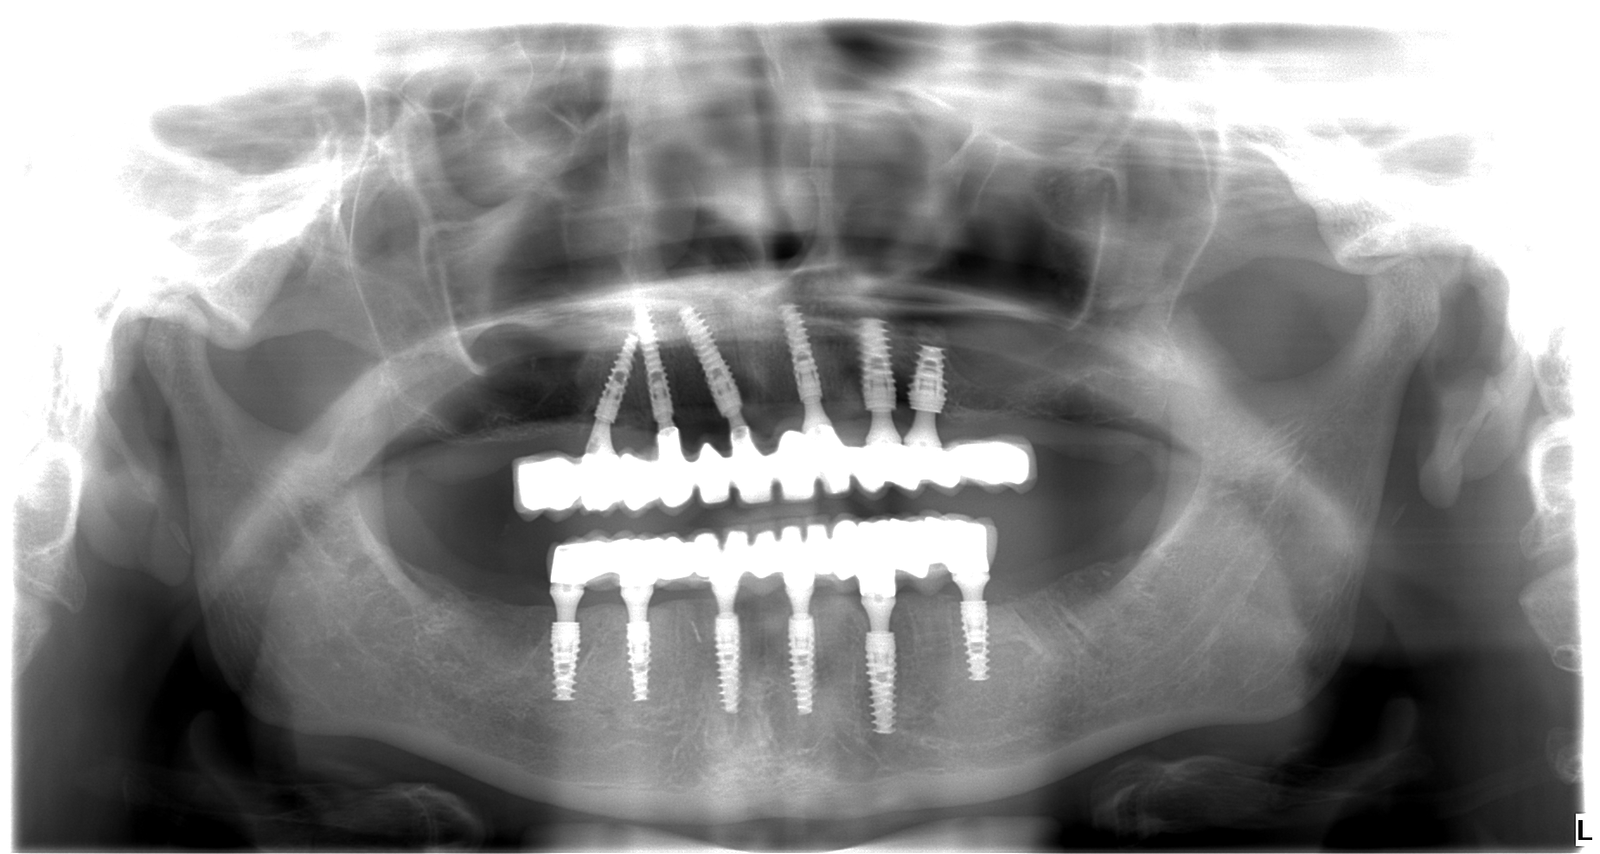

Adriana bola mladá žena, ktorá sa roky trápila s nekompletným a pokazeným chrupom. Hanbila sa smiať, vyhýbala sa foteniu a spoločnosti a spoločenským aktivitám. Rozhodla sa to zmeniť a prišla k nám. Po dôkladnej konzultácii, röntgene a 3D snímke sme jej navrhli plán na mieru: extrakcie nevyhovujúcich zubov, 6 implantátov hore, 6 dole a nový, 12-členný mostík do oboch čeľustí.

2. Zavedenie implantátov: Po extrakciách vám zavedú implantáty. Už počas hojenia získate dočasný mostík vystužený titánom – takže ani jediný deň nezostanete bez zubov.